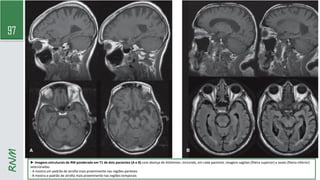

RNM

► Imagens estruturais de RM ponderada em T1 de dois pacientes (A e B) com doença de Alzheimer, incluindo, em cada paciente, imagens sagitais (fileira superior) e axiais (fileira inferior)

selecionadas.

- A mostra um padrão de atrofia mais proeminente nas regiões parietais

- B mostra o padrão de atrofia mais proeminente nas regiões temporais